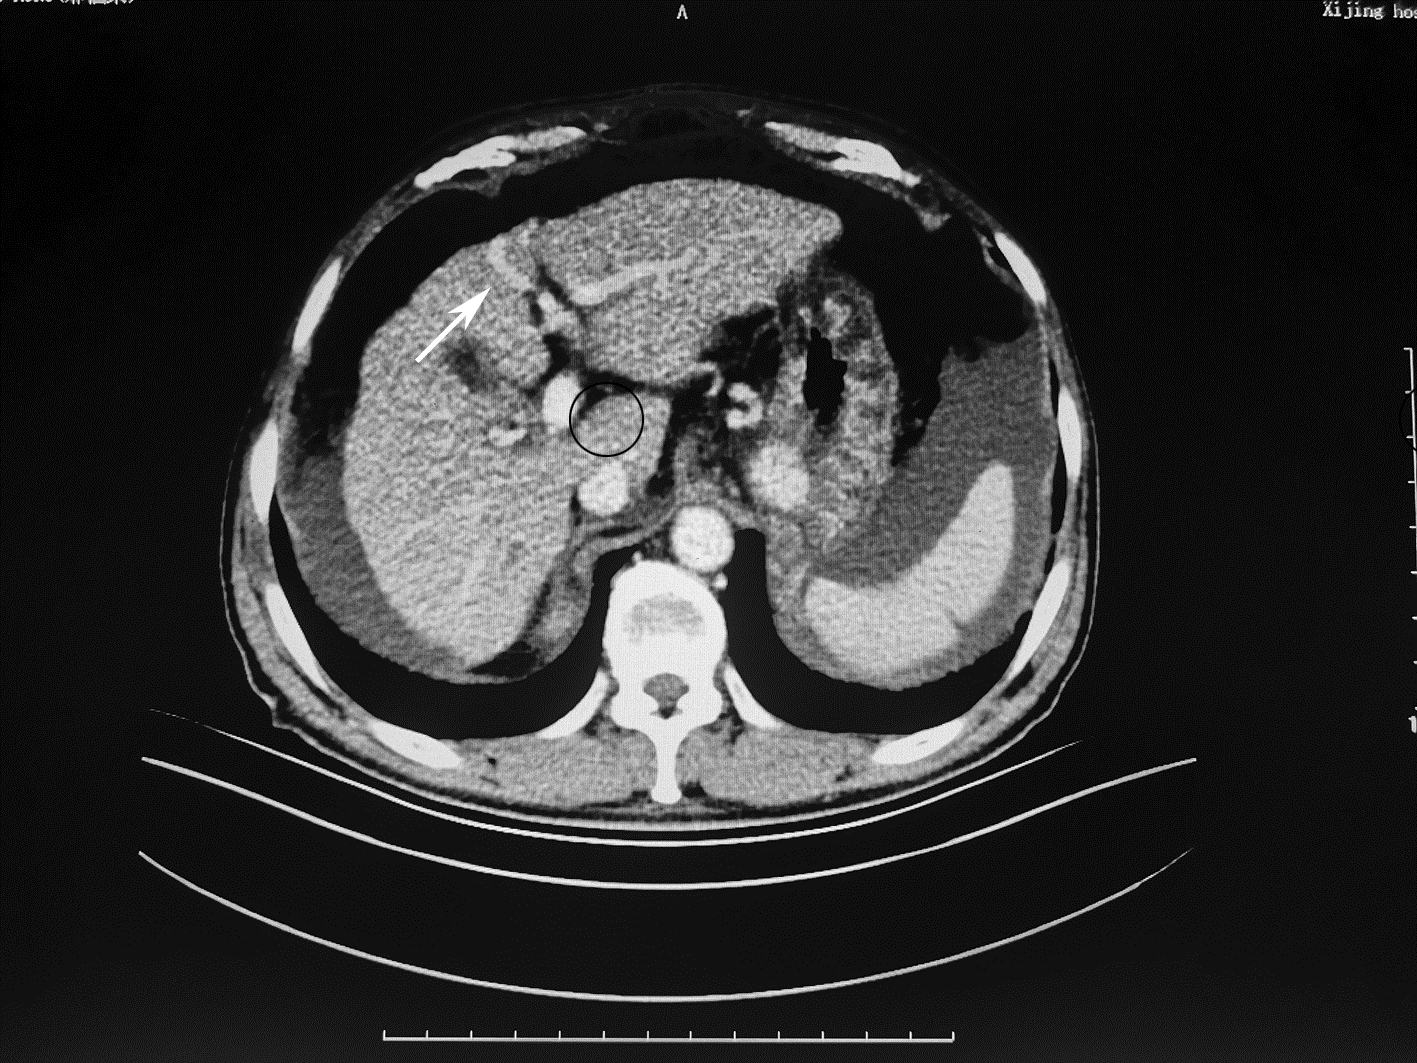

局部栓塞联合靶向免疫综合治疗肝肉瘤样癌1例报告

雷进, 张林枝, 陆荫英, 陈博文, 左石

2022, 38(4): 880-882. DOI: 10.3969/j.issn.1001-5256.2022.04.026

摘要(1323) HTML (453) PDF (3487KB)(82)

摘要: